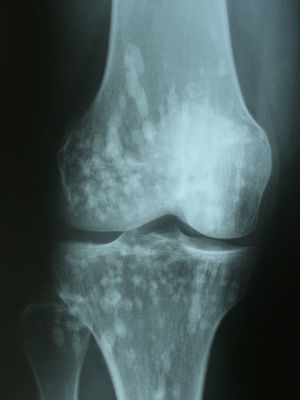

Diagnóstico y evoluciónEn la Rx que aportó la paciente se identificaron unos signos radiológicos que resultaron diagnósticos: numerosas imágenes radiopacas o esclerosas, pequeñas, homogéneas, bien definidas y circulares agrupadas en regiones periarticulares. Era un caso de osteopoiquilosis. No había manifestaciones clínicas con relación a esta enfermedad, tampoco se evidenciaron lesiones cutáneas. Se trataba de un hallazgo casual. A esta paciente se le solicitaron Rx de hombros, manos, pelvis, rodillas y pies (figs. 1–4), y se pudo comprobar que las lesiones halladas en el codo también estaban presentes en todas estas localizaciones. La osteopoiquilosis suele afectar a epífisis y metáfisis de huesos tubulares largos, carpo, tarso, pelvis y escápula de forma simétrica. El tamaño de las lesiones es uniforme.

DiscusiónLa osteopoiquilosis u osteopatía condensante diseminada es una displasia osteosclerótica asintomática. Su aparición antes de los 3 años es infrecuente, aparece tanto en varones como en mujeres. Existen casos hereditarios y esporádicos. Las manifestaciones clínicas suelen faltar, aunque en un 25% de casos pueden encontrarse lesiones cutáneas que consisten en infiltraciones fibrocolágenas, predisposición a la formación de queloides y lesiones similares a las de la esclerodermia. Los hallazgos radiológicos son diagnósticos1. El diagnóstico diferencial debe hacerse con metástasis osteoblásticas, mastocitosis y esclerosis tuberosa2. La distribución simétrica, la afectación de epífisis y metáfisis, y el tamaño uniforme de las lesiones son datos sugestivos de osteopoiquilosis. El aspecto normal de una gammagrafía ósea acabaría de apoyar el diagnóstico.